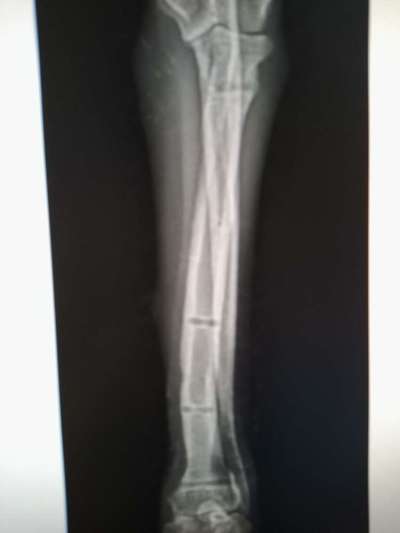

Aufgrund dieser Röntgenaufnahmen wurde am 25.10.23 beschlossen, dass der Fixateur entfernt werden kann.

Auf diesen Aufnahmen, die direkt nach der Entfernung des Fixateurs gemacht wurden, kann man gut erkennen, warum Lucy wieder / noch geschont werden muss.

Mal wieder sind es ihre dünnen Knochen in Verbindung mit ihrem Temperament, die die extreme Schonung erforderlich machen. Sonst bricht der Knochen aufgrund der Löcher, die durch die Fixateur-Drähte entstanden sind.